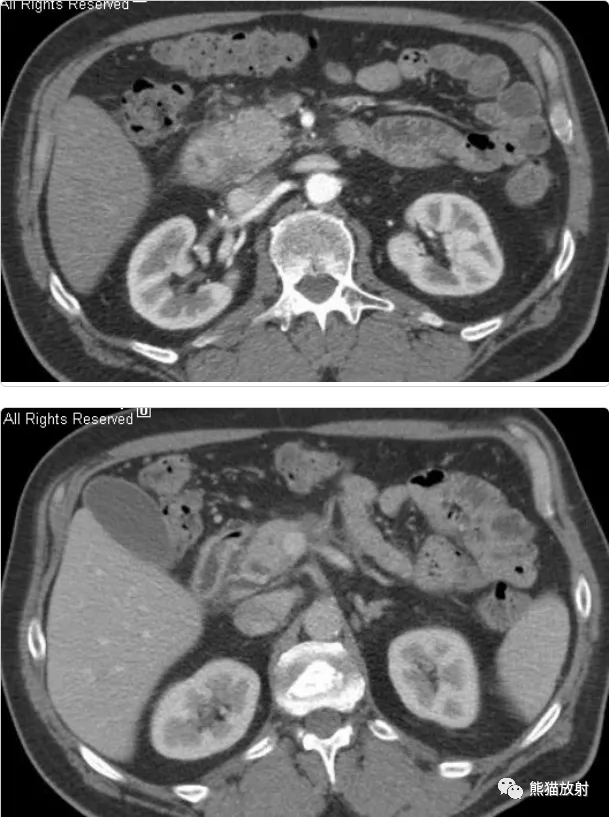

男 , 60岁 , 腹痛、乏力、体重减轻 。 CA19-9正常 。

行上腹部CT增强(动脉期、实质期、冠状MPR)

影像表现:

- 胰头略饱满 , 胰腺实质密度尚均匀;

- 胰十二指肠沟区域间隙浑浊 , 可见等低密度灶 , 不均质轻中度强化;

- 邻近十二指肠壁略增厚 , 强化较明显;

- 主胰管无扩张 , 胆总管略窄;

- 周围未见明显肿大淋巴结 。